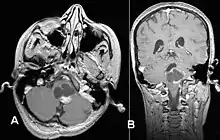

Pilocytic astrocytomas are often cystic, and, if solid, tend to be well-circumscribed. They are characteristically easily seen on computed tomography (CT scans) and magnetic resonance imaging (MRI).

Usually – depending on the interview of the patient and after a clinical exam which includes a neurological exam and an ophthalmological exam – a CT scan and/or an MRI scan will be performed. A special dye may be injected into a vein before these scans to provide contrast and make tumors easier to identify. The neoplasm will be clearly visible.

Visual aspect

Microscopically, an astrocytoma is a mass that looks well-circumscribed and has a large cyst. The neoplasm may also be solid.